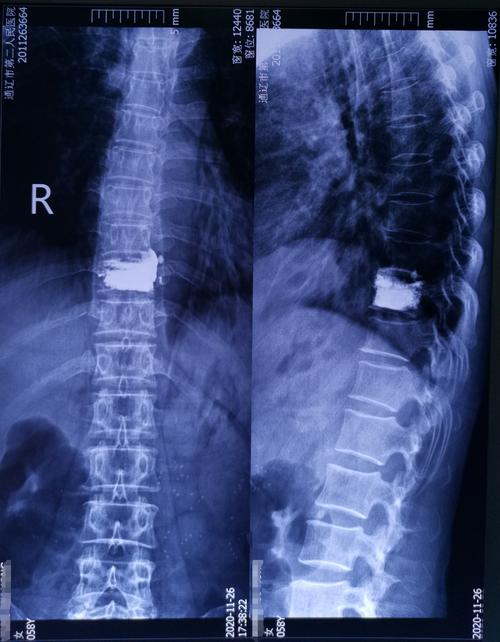

59岁胸椎压缩性骨折患者行椎体成形手术一例

ct示:t12椎体压缩性粉碎性骨折并骨性椎管狭窄严重.

t12椎体压缩性骨折(田欢)